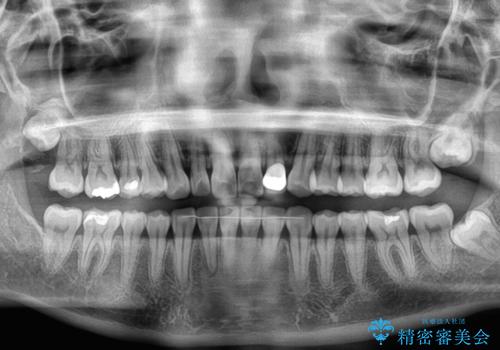

【モニター】前歯のデコボコと小さい前歯 インビザライン矯正とオールセラミッククラウン補綴治療

- 前歯の歯並びと生えてきたときから小さい前歯を気にして来院された患者様です。

上下前歯の歯列不正はインビザラインにより整え、その後に、矮小歯の前歯をオーダーメイドタイプのオールセラミッククラウンにて補綴治療することとしました。

インビザライン矯正の場合、矮小歯を矯正治療後にセラミックとするかどうかを矯正治療開始前に決める必要があるため、悩んでしまう方が多いです。

セラミッククラウンにて大きさを変更することを前提に矯正治療を開始したため、大変満足のいく仕上がりとなりました。